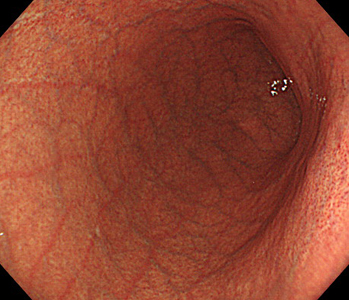

胃内視鏡(胃カメラ)画像

| ◆ 経口内視鏡(高解像度)◆ | ◆ 経鼻内視鏡 ◆ |

| 胃 | 胃(経鼻) |

※ 経鼻内視鏡はカメラの径が細いぶん、解像度が低く暗い画像となり病変の見逃しが多くなる傾向があります。